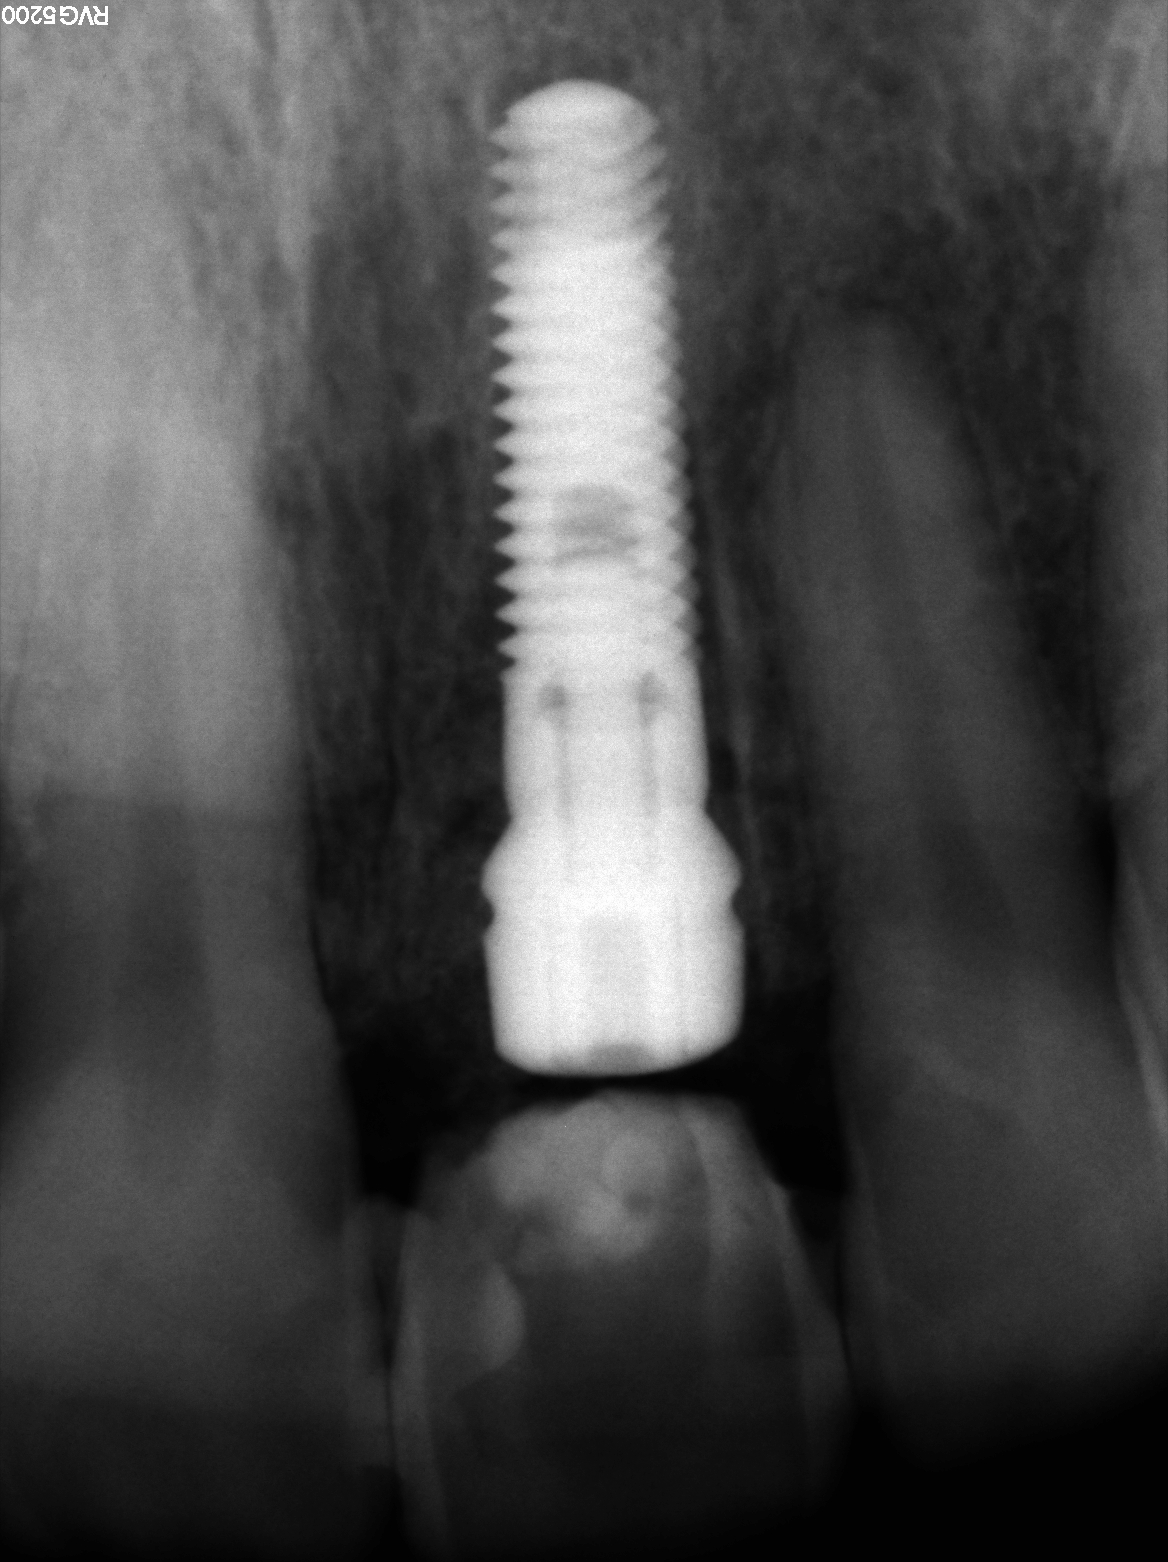

Un implant dentaire est une racine artificielle en titane qui remplace la racine manquante d’une dent naturelle. Il est placé dans la mâchoire inférieure ou supérieure pour remplacer une ou plusieurs dents. Après la période de cicatrisation osseuse, la couronne est fixée au-dessus de l’implant.

→ Pose du ou des implants

Durant cette étape, le praticien pose les implants dentaires pour remplacer les racines manquantes. À l’issue de cette intervention, vous sentirez des implants couverts par la gencive, et qu’ils sont mis en “nourrice” : cela permet à l’os de cicatriser autour des implants.

→ Pose de la prothèse définitive

Après la cicatrisation de l’os et de la gencive, une simple prise d’empreinte comme sur une dent naturelle permettra la réalisation d’une prothèse naturelle et fonctionnelle.